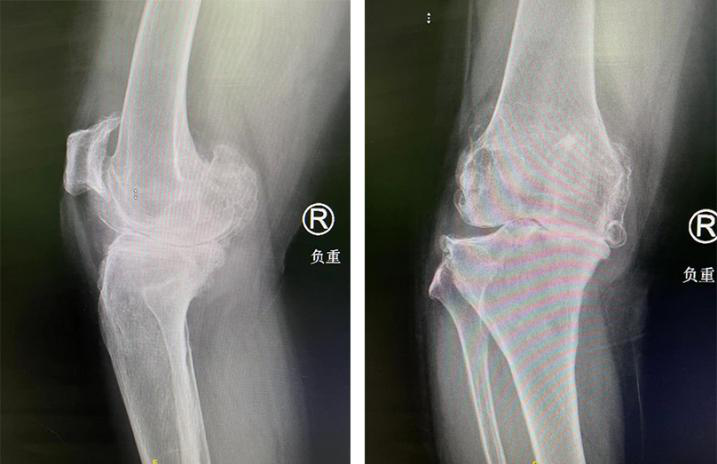

术前

原来,张大姐在20年前双膝关节莫名出现疼痛,尤其是在累了之后,疼痛更是加剧。当时,忙于事业打拼的张大姐觉得这是劳累所致,自己休息休息应该就没事了,所以没放在心上,但随着时间的流逝,双膝关节的疼痛逐渐加重,更是出现关节肿胀、内翻畸形以及活动受限等症状。

这下,可让张大姐警觉起来,开始吃药、打针、按摩等等治疗,起初还有效果,但时间久了又开始复发。直到5年前,张大姐的右膝关节症状加重,出现夜间休息时僵硬的情况,活动范围明显缩小,只能在室内进行活动。即使这样,张大姐的右膝关节有时候疼起来,就连吃镇痛药也无法缓解……

入院后,关节外科郝亮医生为张大姐进行了系统检查,行X线检查提示双膝关节骨关节病。“对于比较严重的膝关节骨性关节炎,尤其是这类经保守治疗后无改善的患者,人工全膝关节置换手术是当下较为针对性的一种治疗方法——用人工关节部件替代损坏的关节,矫正肢体力线,消除膝关节疼痛,维持关节稳定性,从而达到恢复膝关节功能的目的。”郝亮医生介绍道。